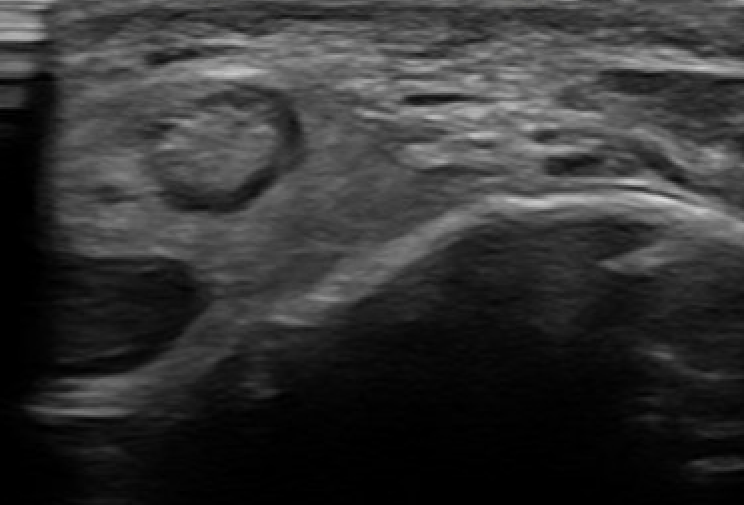

Dynamic Ultrasound

Demonstrates dynamic subluxation

2. Intra-sheath subluxation with intact superior peroneal retinaculum

- 14 patients with painful snapping but could not dislocated out of groove

- ultrasound demonstrated peroneal tendons switching positions

- at surgery superior retinaculum intact with convex peroneal groove

- 10/14 had peroneal tendons switching positions

- 4/14 had a tear in PB through which PL could sublux